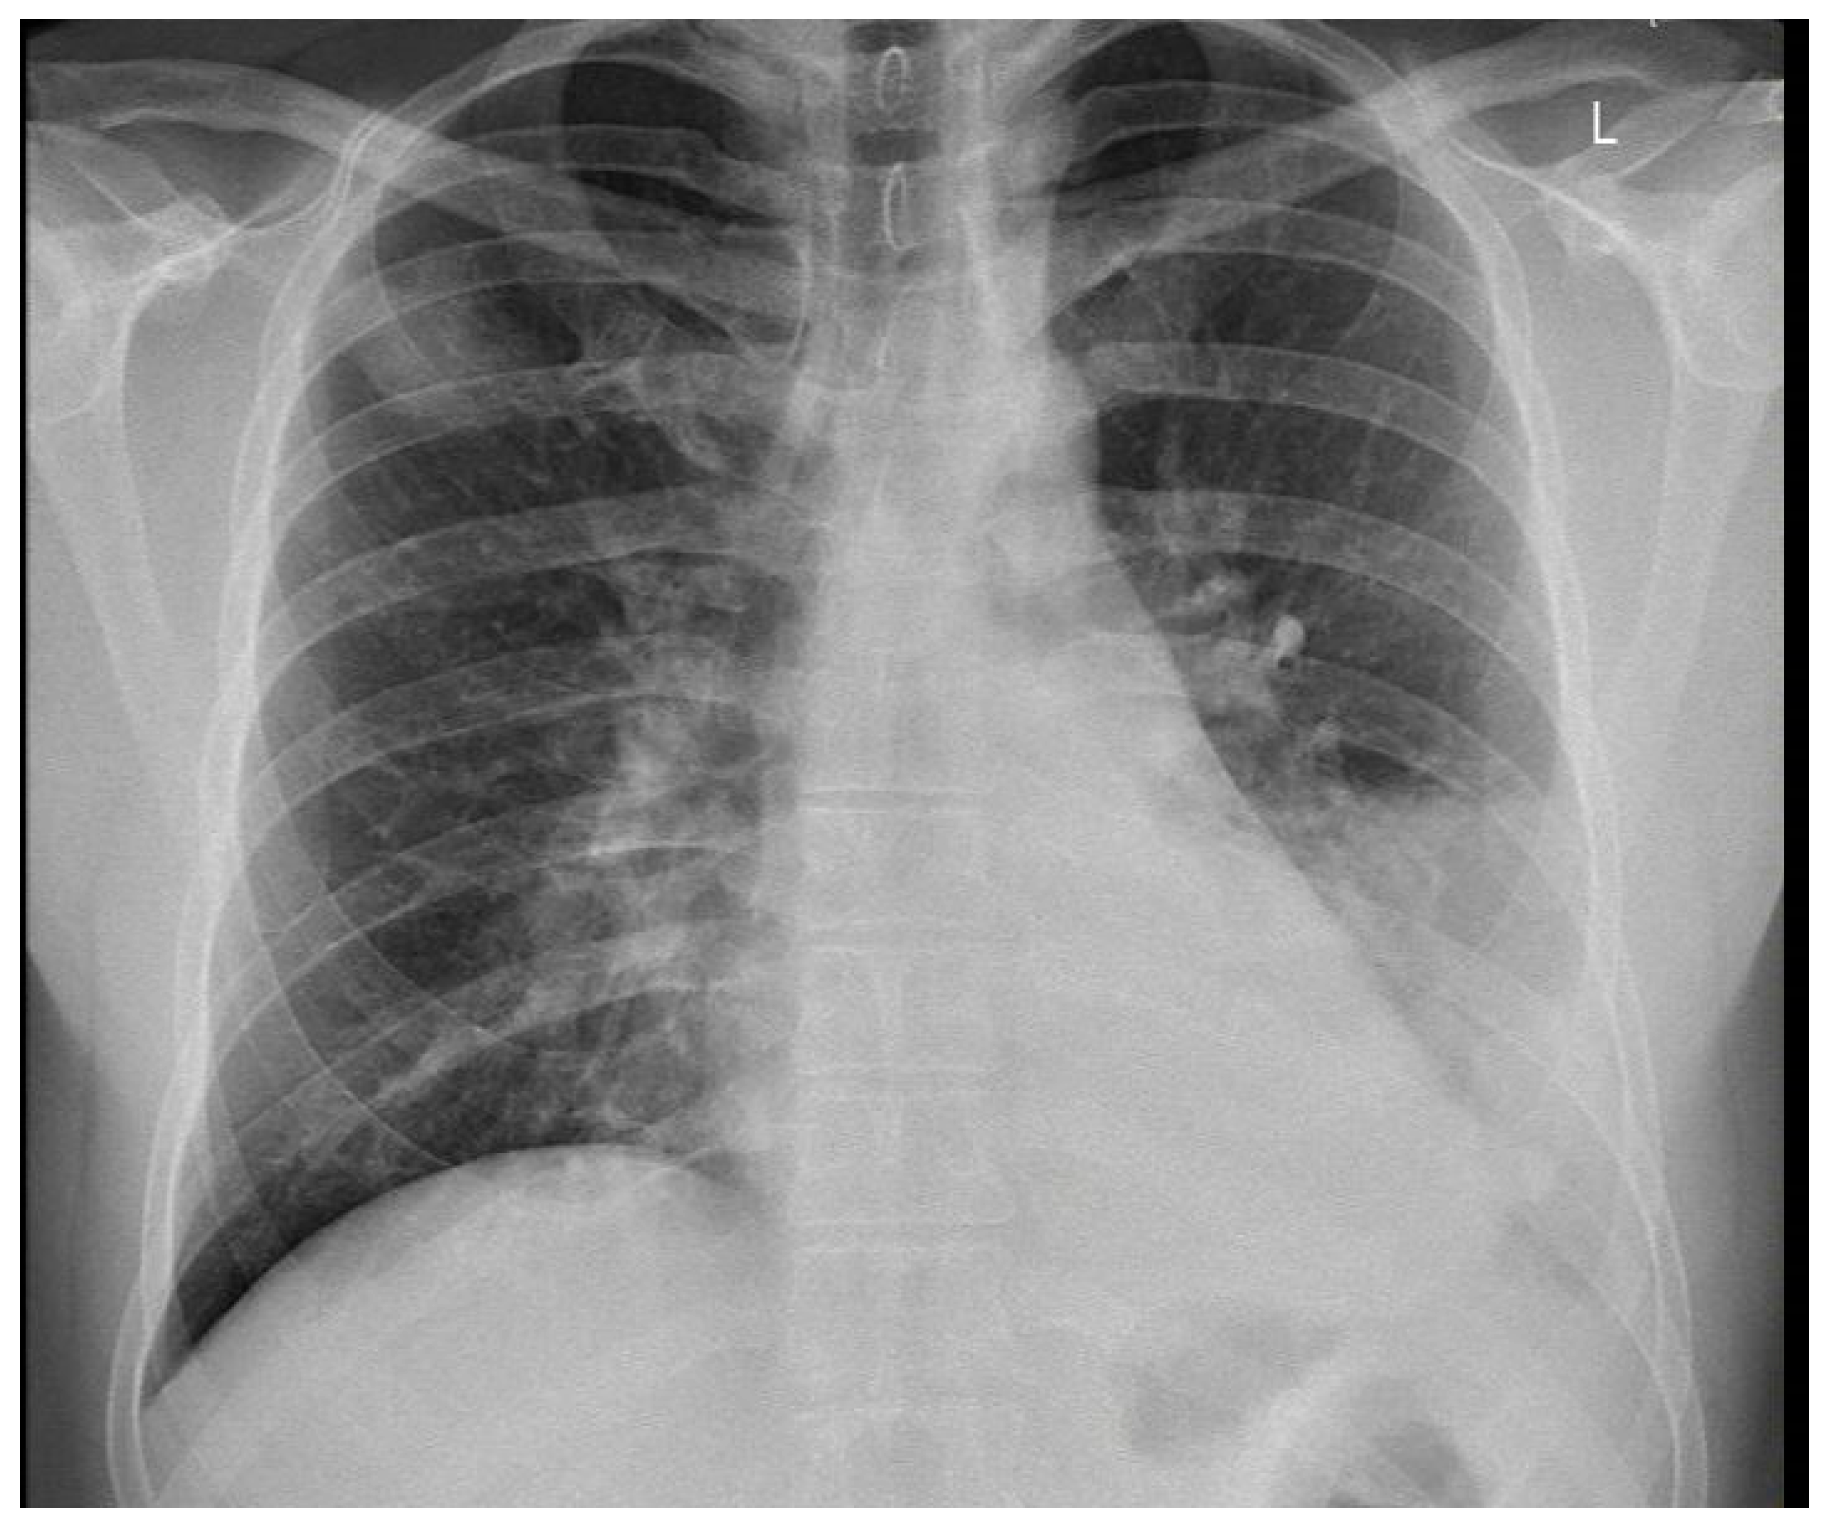

X-ray and CT scans of the chest were performed. The left lung’s lower lobe infiltrates and the right lung’s upper lobe interstitial changes (most probably of an inflammatory nature) were shown, as well as a small amount of fluid in the left pleural cavity (Figure 3 and Figure 4). Several tests were also performed to determine the etiology of the pneumonia. However, blood cultures, an antigen test for SARS-CoV-2, urine tests for Streptococcus pneumoniae, Legionella pneumophila, Cryptococcus sp., and Mycobacterium tuberculosis antigens, and an HIV screening test were all negative. In the following days, empirical antibiotic therapy with ceftriaxone and vancomycin was continued. A rapid improvement in the patient’s clinical condition was observed, as well as a significant decrease in the levels of inflammatory markers. On 22 August 2022, the patient was discharged home in good general condition.

Figure 3. Left lung lower lobe infiltrates are shown, as well as a small amount of fluid in the left pleural cavity at X-ray scan.